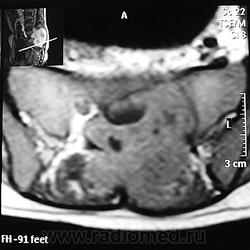

ГМ. СМ. Гигантоклеточная опухоль. +

Гигантоклеточная опухоль рояснично-крестцовой области.